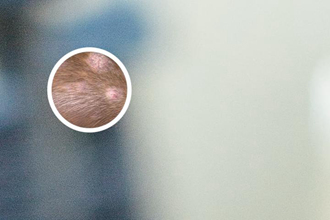

遵義市點(diǎn)陣激光治療白癜風(fēng)后,反黑恢復(fù)時(shí)間并不是一概而論,通常需要2-3個(gè)月左右才能看到顯然效果。但終的恢復(fù)時(shí)間因人而異,與患者的病情嚴(yán)重程度、個(gè)體差異、治療方案的制定以及術(shù)后護(hù)理等諸多因素密切相關(guān)。有些患者可能恢復(fù)較快,而另一些患者則可能需要更長(zhǎng)的時(shí)間才能達(dá)到不錯(cuò)的治療的效果?!白窳x市點(diǎn)陣激光后反黑多久能恢復(fù)”這個(gè)問(wèn)題,沒(méi)有一個(gè)一些的答案,需要結(jié)合個(gè)體情況進(jìn)行綜合評(píng)估。 白癜風(fēng)是一種復(fù)雜的皮膚疾病,其治療過(guò)程需要耐心和堅(jiān)持,患者切勿急于求成。

點(diǎn)陣激光治療白癜風(fēng),是利用激光科學(xué)作用于白斑區(qū)域,刺激黑素細(xì)胞的再生和活性,從而促進(jìn)黑色素的生成。與傳統(tǒng)治療方法相比,點(diǎn)陣激光具有創(chuàng)傷小、恢復(fù)快、治療的效果不錯(cuò)等優(yōu)點(diǎn)。它通過(guò)選擇性地作用于病變區(qū)域,避免了對(duì)周圍正常皮膚的損傷,減少了不良反應(yīng)的發(fā)生。 與其他治療方法相比,點(diǎn)陣激光治療能夠更有效地改善白斑的色素沉著,讓皮膚顏色恢復(fù)均勻。點(diǎn)陣激光并不是適用于所有類型的白癜風(fēng),醫(yī)生會(huì)根據(jù)患者的具體情況進(jìn)行評(píng)估,選擇較合適的治療方案。 “遵義市點(diǎn)陣激光后反黑多久能恢復(fù)”與治療方案的科學(xué)度息息相關(guān)。

判斷點(diǎn)陣激光治療白癜風(fēng)的治療的效果,不能單純依賴時(shí)間,更重要的是觀察白斑部位的色素恢復(fù)情況。通過(guò)觀察白斑顏色是否變深、面積是否縮小、皮膚紋理是否恢復(fù)正常等方面綜合判斷。 治療過(guò)程中,部分患者可能會(huì)出現(xiàn)一些并發(fā)癥,例如色素沉著、皮膚紅腫、瘙癢等。這些通常是暫時(shí)的,一般會(huì)在數(shù)周內(nèi)自行消退。但如果出現(xiàn)嚴(yán)重的感染、疤痕等情況,應(yīng)及時(shí)就醫(yī)。定期復(fù)診監(jiān)測(cè)治療進(jìn)程非常關(guān)鍵,“遵義市點(diǎn)陣激光后反黑多久能恢復(fù)”與治療的效果的終評(píng)估密切相關(guān)。